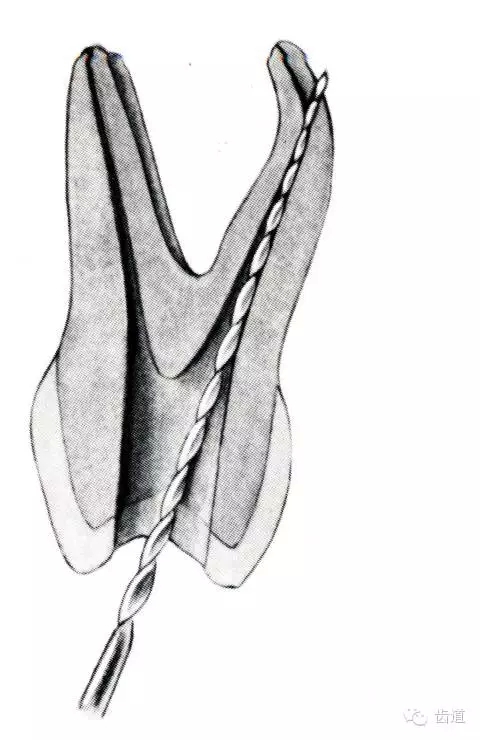

根管壁穿孔多在根管彎曲處。

(4)根管壁形成臺階:先換小號銼去除臺階,再順序擴(kuò)挫。如根管壁穿孔,找到主根管進(jìn)行預(yù)備后,主根管及側(cè)穿道同時充填。在根尖1/3或根尖彎曲處側(cè)穿,根充后,配合根尖手術(shù)——根切+倒充填。